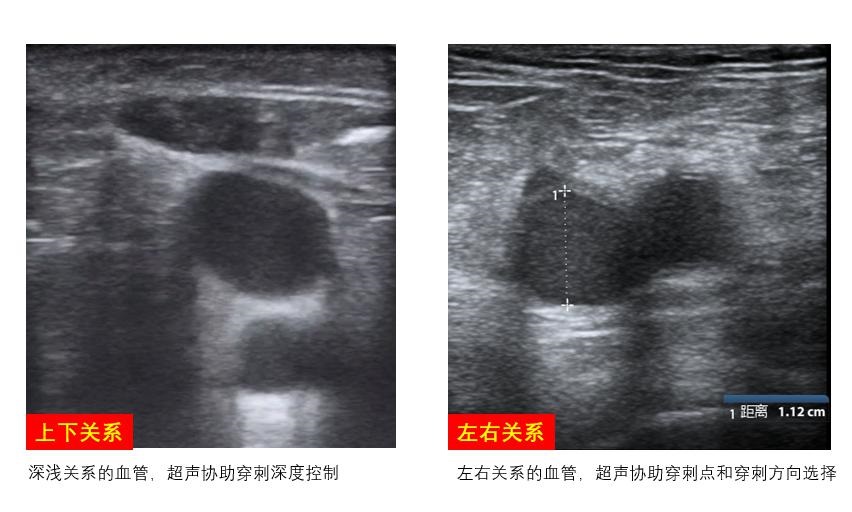

B、穿刺策略制定拟穿刺静脉和相伴行动脉之间的位置关系、属支汇入情况、目标血管走行方向、寻找最佳穿刺点、制定穿刺方向及放置深度等穿刺策略(图 9)。股静脉穿刺点选择建议尽可能避免与腹股沟距离过近,以防穿刺置管时穿透腹膜或损伤腹腔内组织。尽可能避开大隐静脉汇入点、避免损伤静脉瓣、避免ECMO置管对局部血管的损伤,影响ECMO存活患者的长期生活质量。

| 图 9 静脉置管策略 |

B、最佳穿刺点定位观察拟穿刺动脉与伴行静脉之间的位置关系,寻找最佳穿刺点,若超声发现同侧股动静脉之间的距离较近或呈上下叠加关系,则需考虑引流管和回输管分别左、右双腿放置,避免穿刺置管造成局部血管损伤及其他并发症的发生(图 11)。

| 图 11 股动静脉位置关系 |